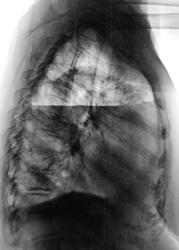

Контроль после лечения в Х.О.

1.dscn0287.jpg2.dscn0287a.jpg3.dscn0288.jpg4.dscn0288a.jpg

Эффект дренирования неоспорим, но - полость сохраняется, и самое главное - а что в пунктате?...неужели - соломенно-желтая?))))

В пунктате - гной